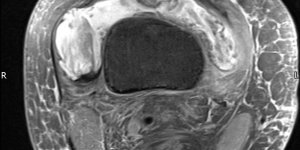

Monoarthropathy – Knee | Cases

Published on Jan 12, 2021

27 female 10 Year history of Knee pain. Used to do running but now doesn’t due to pain. Previous diagnosis – Bakers Cyst which was drained. Examination No effusion Full ROM, no pain with overpressure NAD ligaments NAD meniscal test (McMurrays) Cyst present in Popliteal fossa over gastrocnemius region. Non tender MRI requested to ascertain cause [...] Read more